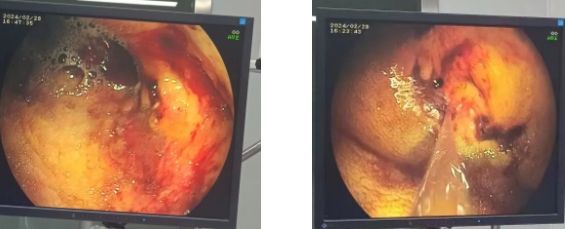

病例四:2024年2月28日,中年男性,胃肿瘤,反复便血,气管插管全麻下行胃镜止血,止血药粘膜下注射、冲洗,止血效果立竿见影。